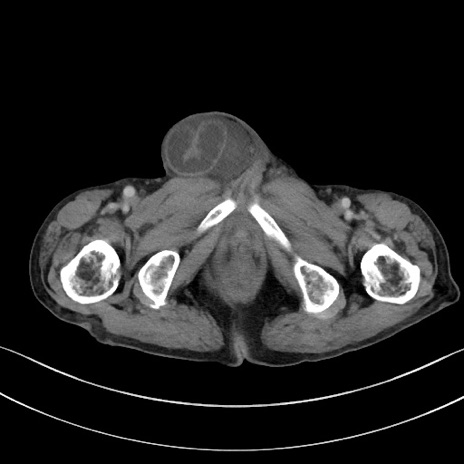

症例3(横断像)

【症例】 70歳代男性

【主訴】右鼠径部腫瘤、疼痛

【現病歴】本日朝より上記主訴あり、受診。

【既往歴】膀胱癌にて膀胱全摘、両側尿管皮膚瘻

【データ】WBC 5600、CRP 0.56